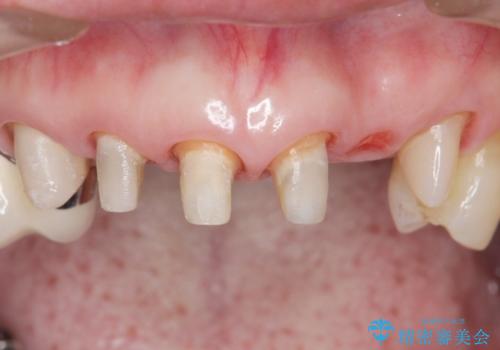

被せ物を除去したところ根管治療後の処置が不十分であったため、ファイバーコア(金属を用いない強くてしなやか材質の土台)を植立したのち、ジルコニアセラミッククラウンによる治療を行いました。

また、古い被せ物はブリッジではない右上321も連結されていましたが、1本1本の歯の動揺がなく連結する必要がないと判断し単冠による補綴を行いました。